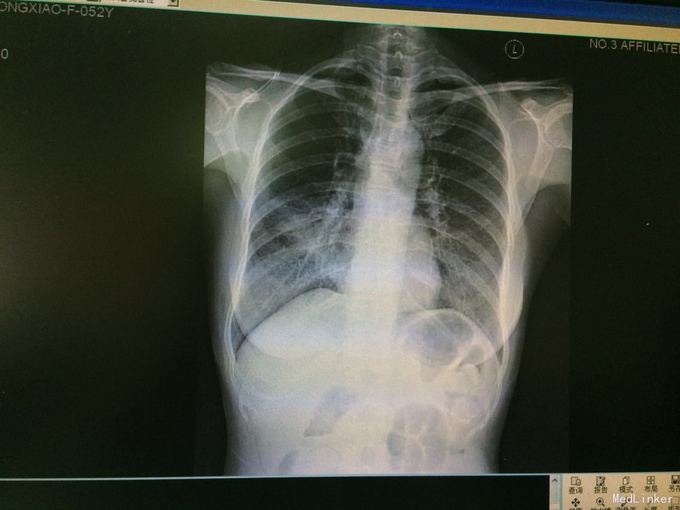

52岁女性,10余年前确诊鼻咽癌,并行放疗2次,5年前开始出现张口中度受限、言语轻度模糊不清、饮食饮水轻度呛咳。 主诉:反复咳嗽、咳痰15天。 现病史:15天前出现咳嗽咳痰,痰为白色稀水样,易咳出,外院查胸片示双肺感染,以右肺中叶明显,遂入院。

随访:患者咳嗽咳痰明显好转,要求出院,复查胸片示肺炎较前吸收,遂办理带药出院。嘱其1周后门诊复诊。 讨论:该病例属典型而较为简单的肺炎,结合实验室及影象结果可诊断。就该患者而言,有鼻咽癌放疗史,现有进食呛咳等后遗症,此次肺炎考虑其吸入性因素可能性大,且不排除以后反复并发吸入性肺炎可能。